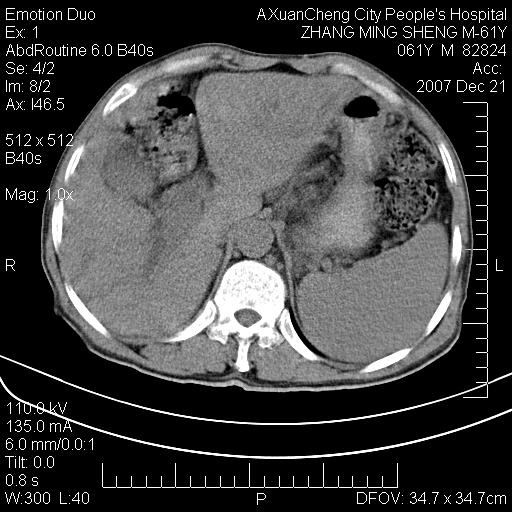

标题: CT11031:M61Y,胰腺占位 [打印本页]

标题: CT11031:M61Y,胰腺占位

大家侃侃门静脉和胆管系统怎么回事,肝内转移?

胰腺癌肝转移

胰腺体部稍宽,其内小片样低密度灶性质?

1,肝硬化,脾大.

2,肝内多发结节状低密度占位,伴门脉及肠系膜上v栓子形成.考虑a;门脉及肠系膜上v血栓后肝改变.b;弥漫型肝癌伴门脉及肠系膜癌栓.

肝硬化,门脉高压,脾肿大;弥漫性肝癌,肝内、门脉、腹膜后淋巴结转移,肝内外胆管扩张,胰头区占位,建议mr检查

胰腺癌伴肝内转移;门脉、肠系膜上v癌栓形成。

考虑为:胰腺癌伴肝脏转移、腹膜后淋巴结转移,门静脉及肠系膜上静脉瘤栓形成。

胰体尾癌伴肝内转移,门静脉及肠系膜上静脉瘤栓形成.

肝硬化,脾大. 胰腺癌伴肝内转移;门脉、肠系膜上v癌栓形成。